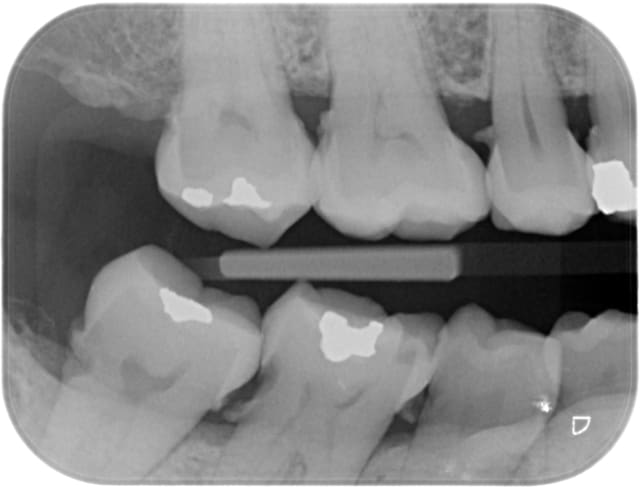

Comme vous le voyez sur la deuxième radio j'ai essayé de bidouiller mais le résultat est crade (en plus y a encore du tartre !) et non satisfaisant.

Sur l'aspect restauratif, que peut-on proposer de viable (en dehors de extrac implants) sur ce genre de cas ?